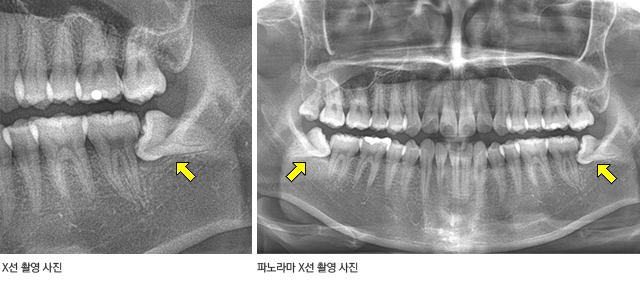

환자의 병력 청취를 통한 문진과 일상적인 방법의 구강검사를 통한 시진, 촉진 그리고 방사선 사진 촬영을 통해 대개의 진단이 가능하다. 경미한 증상은 몇 개의 치아만 볼 수 있는 치근단 사진으로 확인이 가능하나 위치 이상이나 매복, 매몰 등 전반적인 이상 유무를 확인하기 위해서는 전체 치아와 턱뼈의 상태를 한눈에 볼 수 있는 파노라마 사진 촬영이 권장된다.

제3대구치 방사선 검사